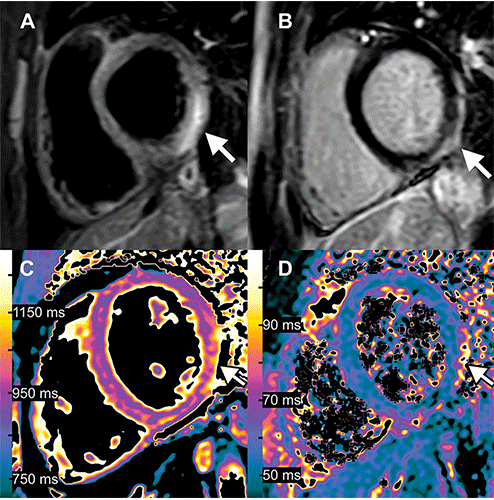

Второе место заняла статья Александра Исаака, Андреаса Фейсста и Джулиана А. Люткенса под названием «Миокардит после вакцинации против COVID-19». 2022 год стал третьим годом подряд, когда изображение, связанное с COVID, было отмечено среди главных претендентов на получение награды « Изображения в радиологии ». все результаты исследований одного возраста.

1-е место, занявшее второе место в 2022 году, лучшие изображения

Изображения 15-летнего мальчика с миокардитом после вакцинации против COVID-19. Через день после получения второй дозы вакцины у него появились лихорадка, миалгия и перемежающаяся тахикардия. (A) Т2-взвешенная МРТ с коротким временем инверсии и восстановлением с инверсией и восстановлением при 1,5 Тл в проекции по короткой оси показывает очаги высокой интенсивности сигнала (стрелка) в базально-латеральной и нижней стенках, что указывает на отек миокарда. (B) Изображение позднего усиления гадолинием в проекции по короткой оси показывает соответствующее линейное субэпикардиальное усиление (стрелка), указывающее на воспалительный некроз миокарда. (C) Т1-картирование и (D) Т2-картирование в проекции по короткой оси показывают повышенные Т1 и Т2 в средней части боковой и нижнелатеральной стенок желудочка (стрелка на С и D), что указывает на острое повреждение миокарда (очаговый Т1, 1165 мс; очаговый Т2). , 70 мс; пороговые значения для острого миокардита, специфичные для учреждения: T1global ≥1000 мс, Общий T2 ≥55,9 мс).